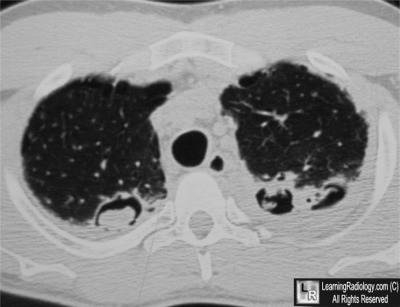

- 49 year-old with a previous history of sarcoid who develops hemoptysis

Axial CT Scan of the Upper Chest

5. Aspergilloma

Aspergilloma

General Considerations

- Caused by Aspergillus fumigatus-soil

fungus - Non-invasive Aspergillosis

- Colonization of pre-existing cavity

- Most frequently TB cavity or Sarcoid

49 year-old with a previous history of sarcoid who develops hemoptysis |